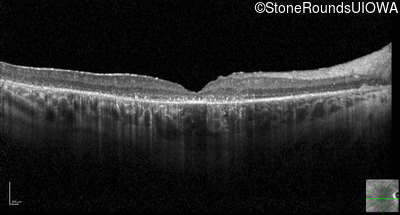

Optical Coherence Tomography - Right - 20/125 -2

Exemplar / OCT Stack

OCT Stack